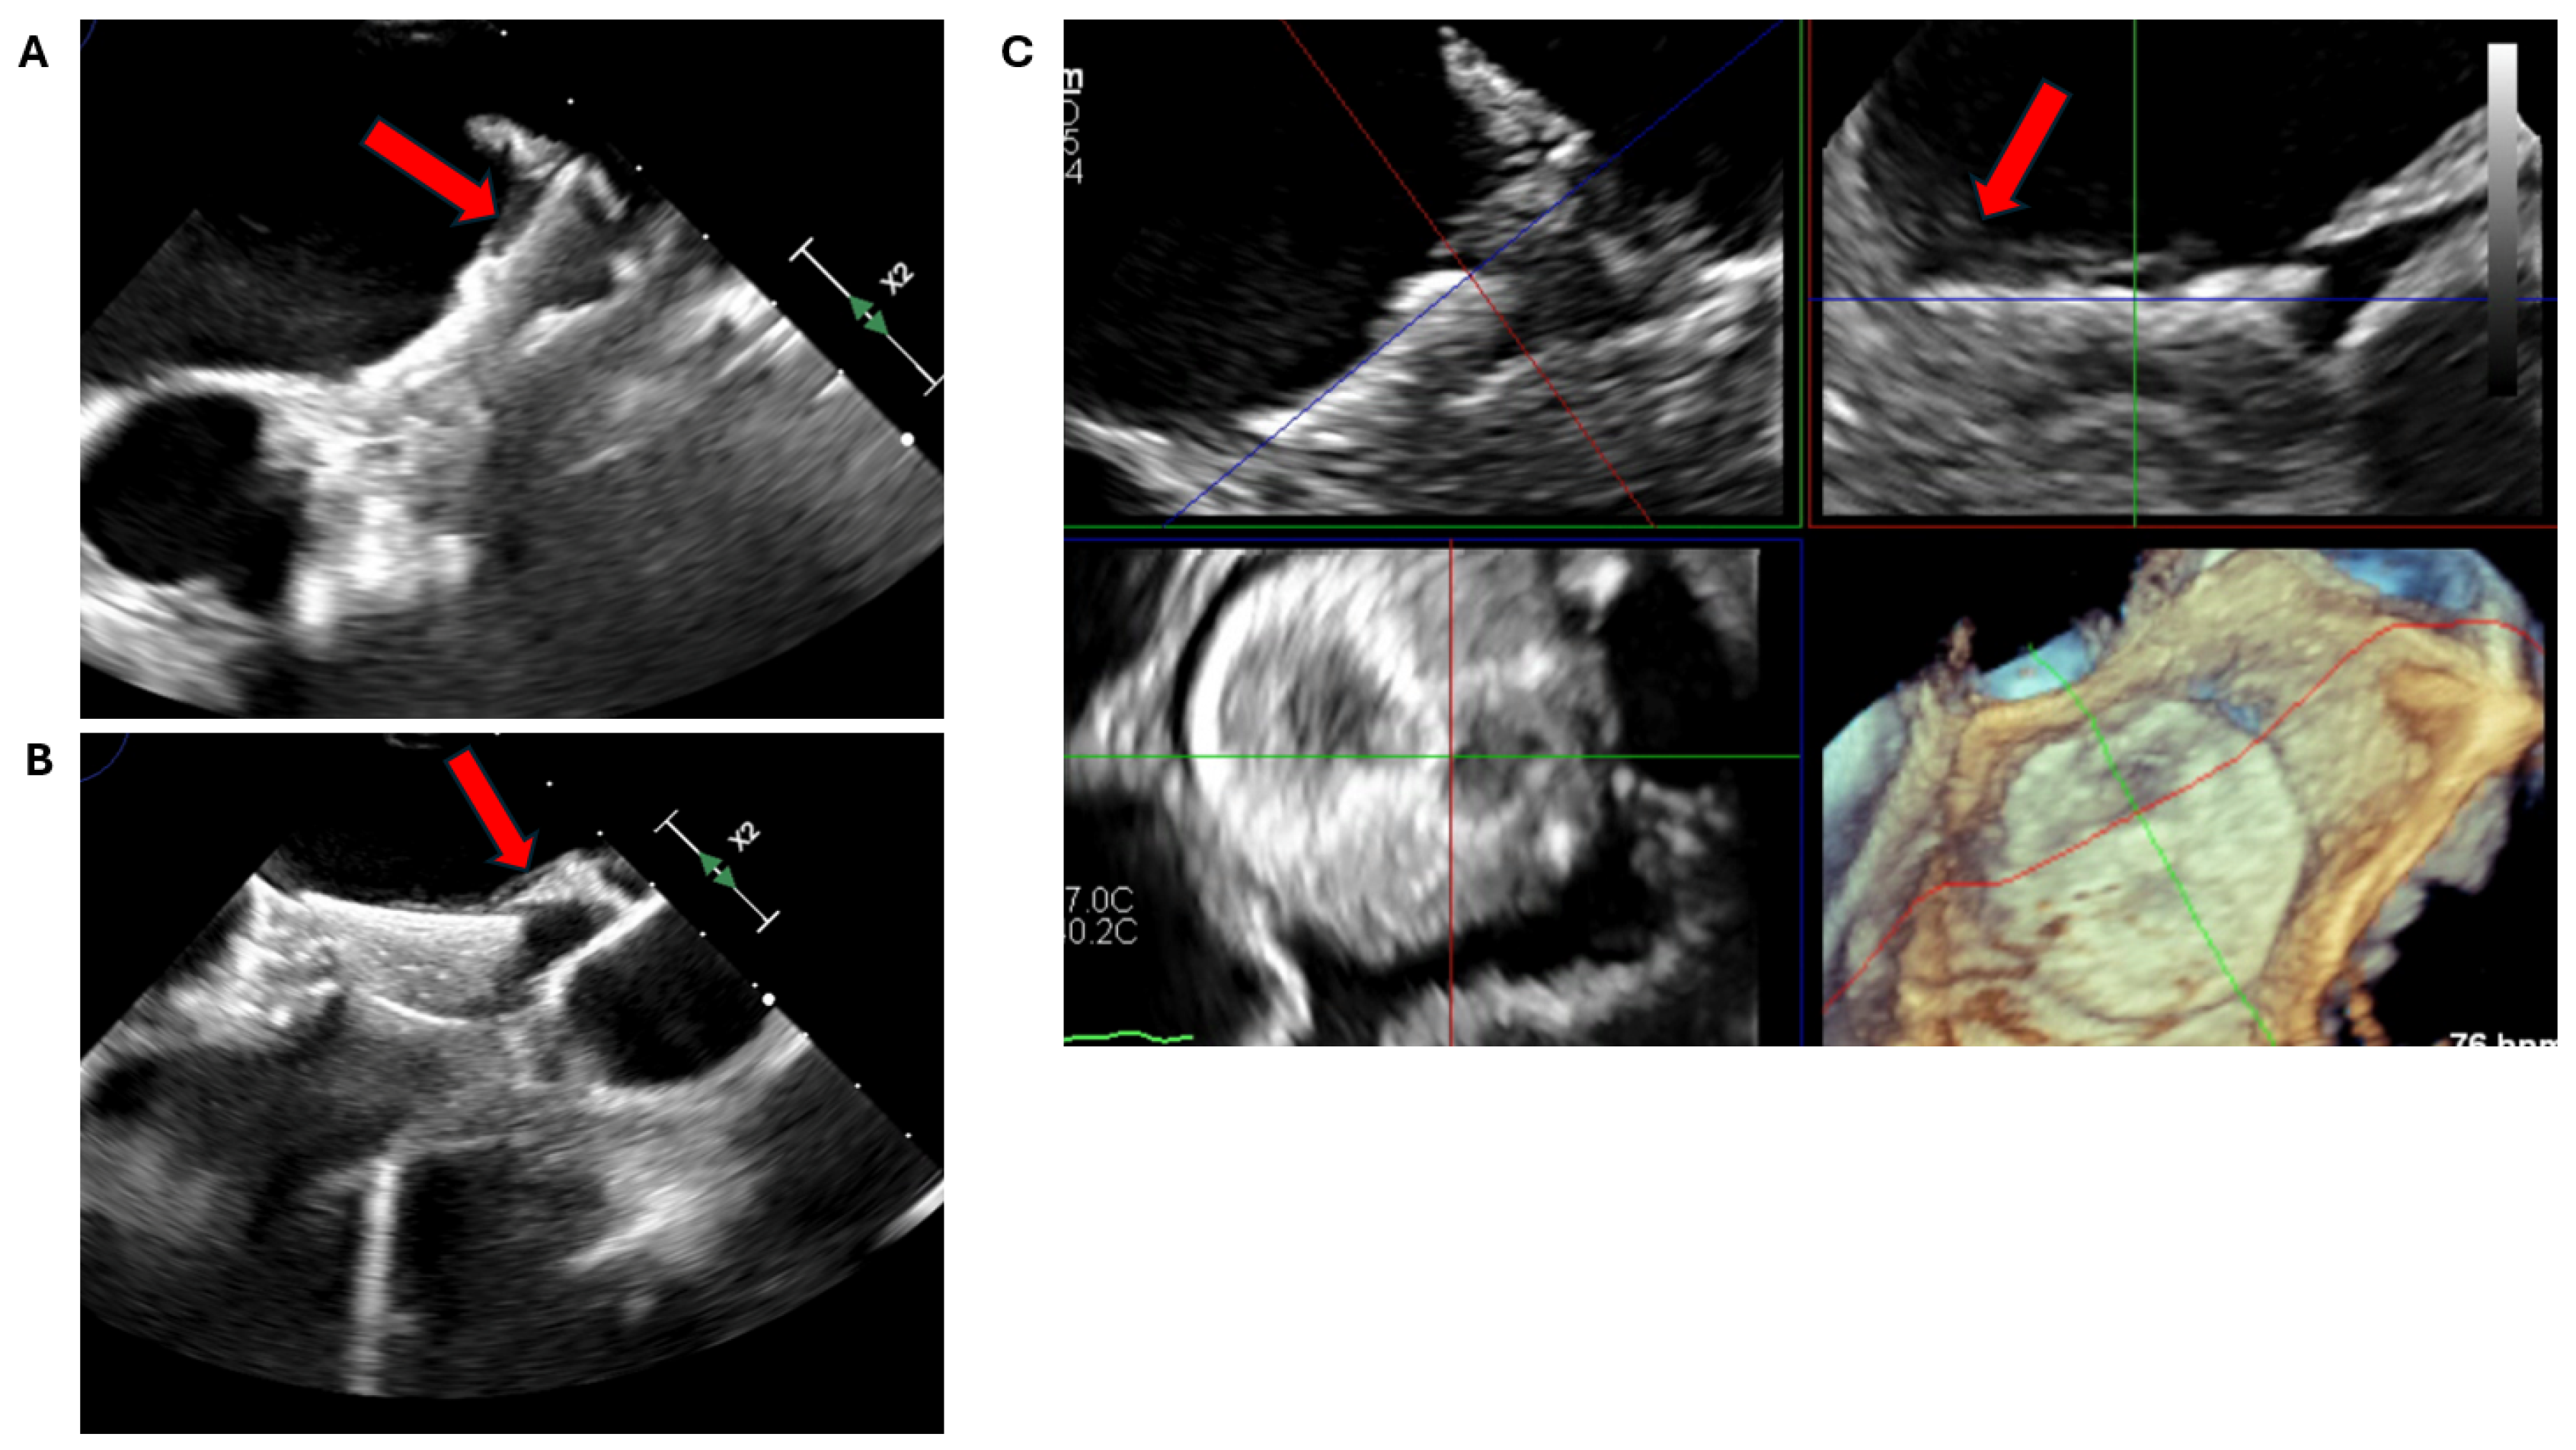

2.2. Transoesophageal Echocardiography

2.2.3. Intra-Procedural TOE

3.1. Device Position and Embolization

3.2. Peri-Device Leaks

3.3. Device-Related Thrombus

3.4. Pericardial Effusion and Device Erosion